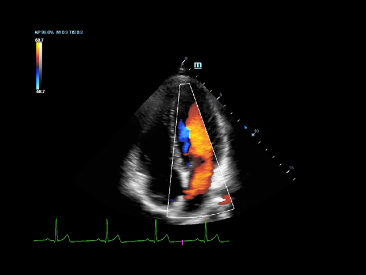

eXceeding Experience

Pengalaman dengan tingkat produktivitas yang tinggi

Pengalaman yang melampaui dalam pemindaian menghasilkan lebih banyak fokus pasien untuk pemeriksaan berkualitas tinggi dalam kejelasan dan kemudahan penggunaan. X-Insight memberikan kemudahan penggunaan yang luar biasa dengan ergonomi yang lebih baik, pemindaian yang lebih mudah, dan manajemen yang fleksibel, bahkan di luar ekspektasi Anda.